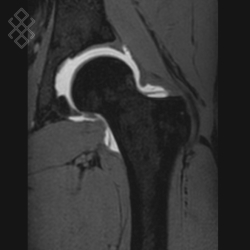

Arthro-IRM de la Hanche

La durée de l'examen est d'environ 20 minutes. Pour repérer la zone souahitée, le radiologue fera une scopie. Ensuite, il effectuera une désinfection puis une anesthésie locale. Pour l'injection du produit de contraste à base de gadolinium, il introduira une aiguille dans la zone repérée, puis il appliquera un pansement étanche. Enfin, vous serez installés afin d'effectuer l'IRM de la hanche.